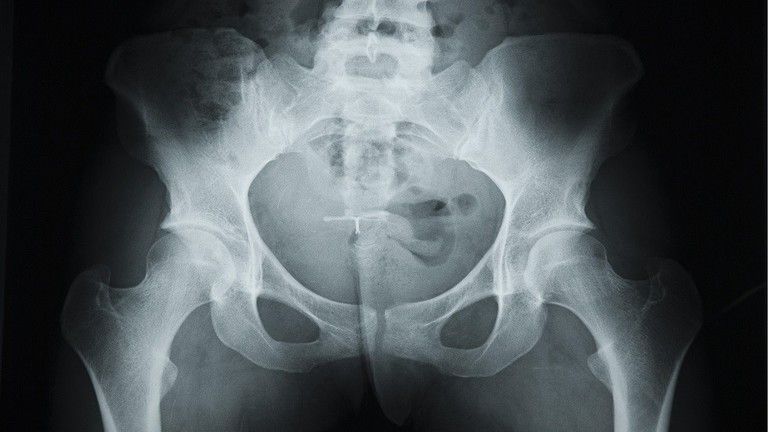

قرر الأطباء بعد اشتباههم بوجود كسر في حوض رجل (63 سنة) لم يكشف عن اسمه، بعد سقوطه في الشارع، فحصه بالأشعة السينية. ولكن الصور أظهرت عدم وجود أي كسر في عظام الحوض، ولكن عضوه الذكري يتحول تدريجيا إلى عظم، نتيجة تطور الخلايا العظمية فيه، وهذا يحصل عادة نتيجة ظاهرة نادرة جدا سجلت مثلها أقل من 40 حالة في العالم حتى الآن.

ووقعت هذه الحادثة في مدينة نيويورك قبل بضعة أشهر، وبقيت الصور الشعاعية تحت تصرف أطباء المستشفى، ما يسمح بالحديث عن حالة جديدة لما يسمى "التعظم" أي التحول التدريجي لأي عضو في الجسم إلى عظم.

ووفقا للخبراء التحول التدريجي للعضو الذكري إلى عظم، سببه مرض بيروني، حيث تسبب الندب الداخلية بتغير شكله. كما أن أنسجة القضيب قد تصبح صلبة نتيجة تراكم أملاح الكالسيوم في مناطق معينة، نتيجة ورم ومشكلات في الغدة الدرقية أو أمراض الكلى.

يمكن تشخيص الحالة فقط بواسطة الأشعة السينية، ولعلاجها أو وقف تطورها تستخدم الأدوية المضادة للالتهابات، وعند مراحلها الأخيرة لا بد من التدخل الجراحي.